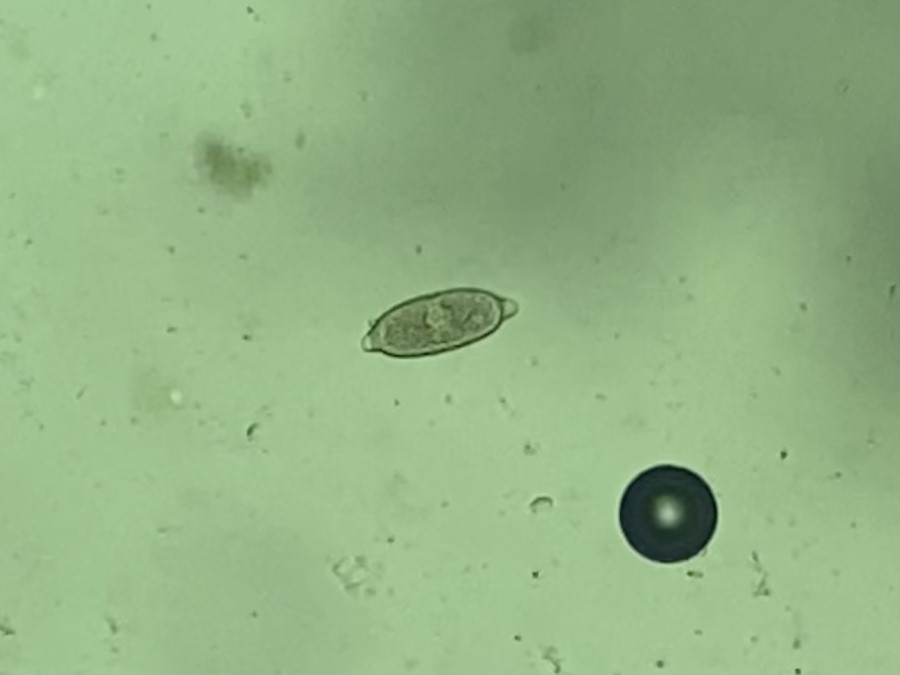

Vista 2 Nematodo gastrointestinal

Nematodo gastrointestinal

Datos taxonómicos

Género:

Capillaria

Especie:

spp

Nombre común: